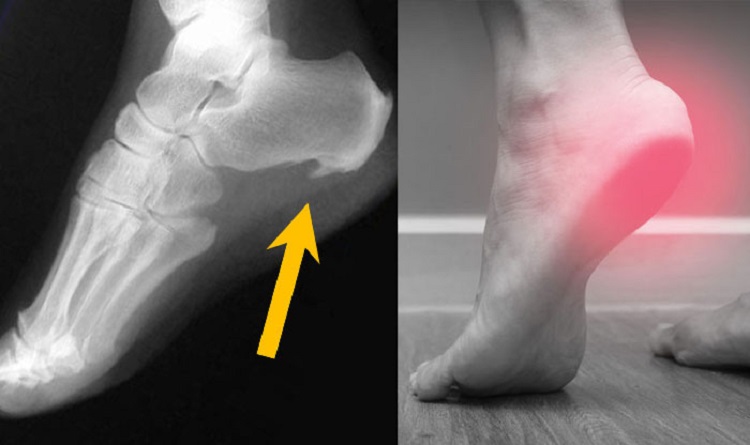

درباره این بیماری، دکتر احمد موذن زاده، فیزیوتراپیست و رئیس انجمن فیزیوتراپی ایران به خبرآنلاین میگوید: «معمولاً افرادی که خار پاشنه دارند، دچار درد استخوان پاشنهی پا در زمان بیدار شدن از خواب هستند.»

او ادامه میدهد: «این افراد بعد از بیدار شدن از خواب و هنگام شروع راه رفتن به محض اینکه پای خود را روی زمین قرار بدهند درد شدیدی را در ناحیه پاشنه احساس میکنند البته ممکن است بعد از مقداری راه رفتن و قدم زدن میزان درد کاهش پیدا کند.»

وی با اشاره به علل ابتلای بیماران به خار پاشنه بیان میکند: «ایجاد خار پاشنه نشانه استرس فیزیکی بیش از حد تحمل بر استخوان پاشنه و استخوان سازی است، طبیعی است که ایستادن طولانی مدت، استفاده از کفشهای نامناسب مانند کفشهایی که کفی سفت و تخت دارند، و البته وزن زیاد به همراه کم تحرکی میتواند از عوامل اصلی ایجاد خار پاشنه باشد.»

رئیس انجمن فیزیوتراپی ایران میگوید: «افردی که دچار خار پاشنه هستند ممکن است مشکلاتی مانند کوتاهی تاندول آشیل داشته باشند، کوتاهی تاندول آشیل میتواند از عوارض استفاده از کفشهای پاشنه بلند خصوصاً در زنان باشد.»

موذنزاده در پایان بیان میکند: «توصیه ما این است که افراد با داشتن چنین علائمی حتما به پزشک مراجعه کنند و از پاشنه پا عکسبرداری شود، با این اقدام مشخص میشود آیا فرد دچار خار پاشنه شده است یا صرفاً التهاب نیام کف پا دارد، البته التهاب نیام کف پا درصورت ادامه داشتن میتواند منجر به بروز خار پاشنه هم شود.»